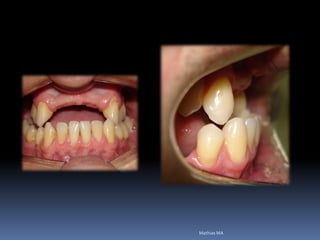

Ausência ou perda dental x implantes

Periodonto íntegro               perdas de suporte

Atrofias ósseas x implantes

Procedimentos reconstrutivos       Compensação protética

prognóstico

favorável                        desfavorável